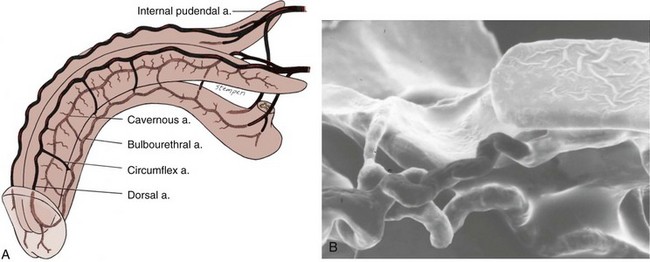

The source of penile blood is usually the internal pudendal artery, a branch of the internal iliac artery (Fig. 23–3A). In many instances, however, accessory arteries exist, arising from the external iliac, obturator, and vesical and femoral arteries, and they may in some men constitute the dominant or only arterial supply to the corpus cavernosum (Breza et al., 1989). In a study of 20 fresh human cadavers, Droupy and colleagues (1997) reported three patterns of penile arterial supply: type I arising exclusively from internal pudendal arteries (3/20); type II arising from both accessory and internal pudendal arteries (14/20); and type III arising exclusively from accessory pudendal arteries (3/20). Nehra and colleagues (2008) studied 79 consecutive patients with a history of erectile dysfunction (ED) and noted that 35% had an accessory pudendal artery, typically arising from the obturator artery. In these men, the accessory pudendal was the dominant blood supply in 54% and the only corporal blood supply in 11%. The importance of accessory pudendal artery preservation during radical prostatectomy was demonstrated by Mulhall and colleagues, who reported more rapid recovery of sexual function in men who underwent artery-sparing radical prostatectomy (Mulhall et al, 2008).

Figure 23–3 A, Penile arterial supply. B, Scanning electron micrograph of a human penile cast showing helicine arteries opening directly into the sinusoids without intervening capillaries.

The internal pudendal artery becomes the common penile artery after giving off a branch to the perineum. The three branches of the penile artery are the dorsal, bulbourethral, and cavernous. Distally, they join to form a vascular ring near the glans. The dorsal artery is responsible for engorgement of the glans during erection. The bulbourethral artery supplies the bulb and corpus spongiosum. The cavernous artery effects tumescence of the corpus cavernosum and enters it at the hilum of the penis, where the two crura merge. Along its course, it gives off many helicine arteries, which supply the trabecular erectile tissue and the sinusoids (Fig. 23–3B). These helicine arteries are contracted and tortuous in the flaccid state and become dilated and straight during erection.